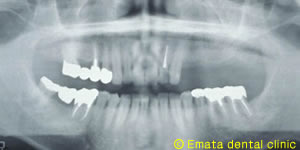

上顎の入れ歯があわない。自分の歯のように食べたい。

Before

After